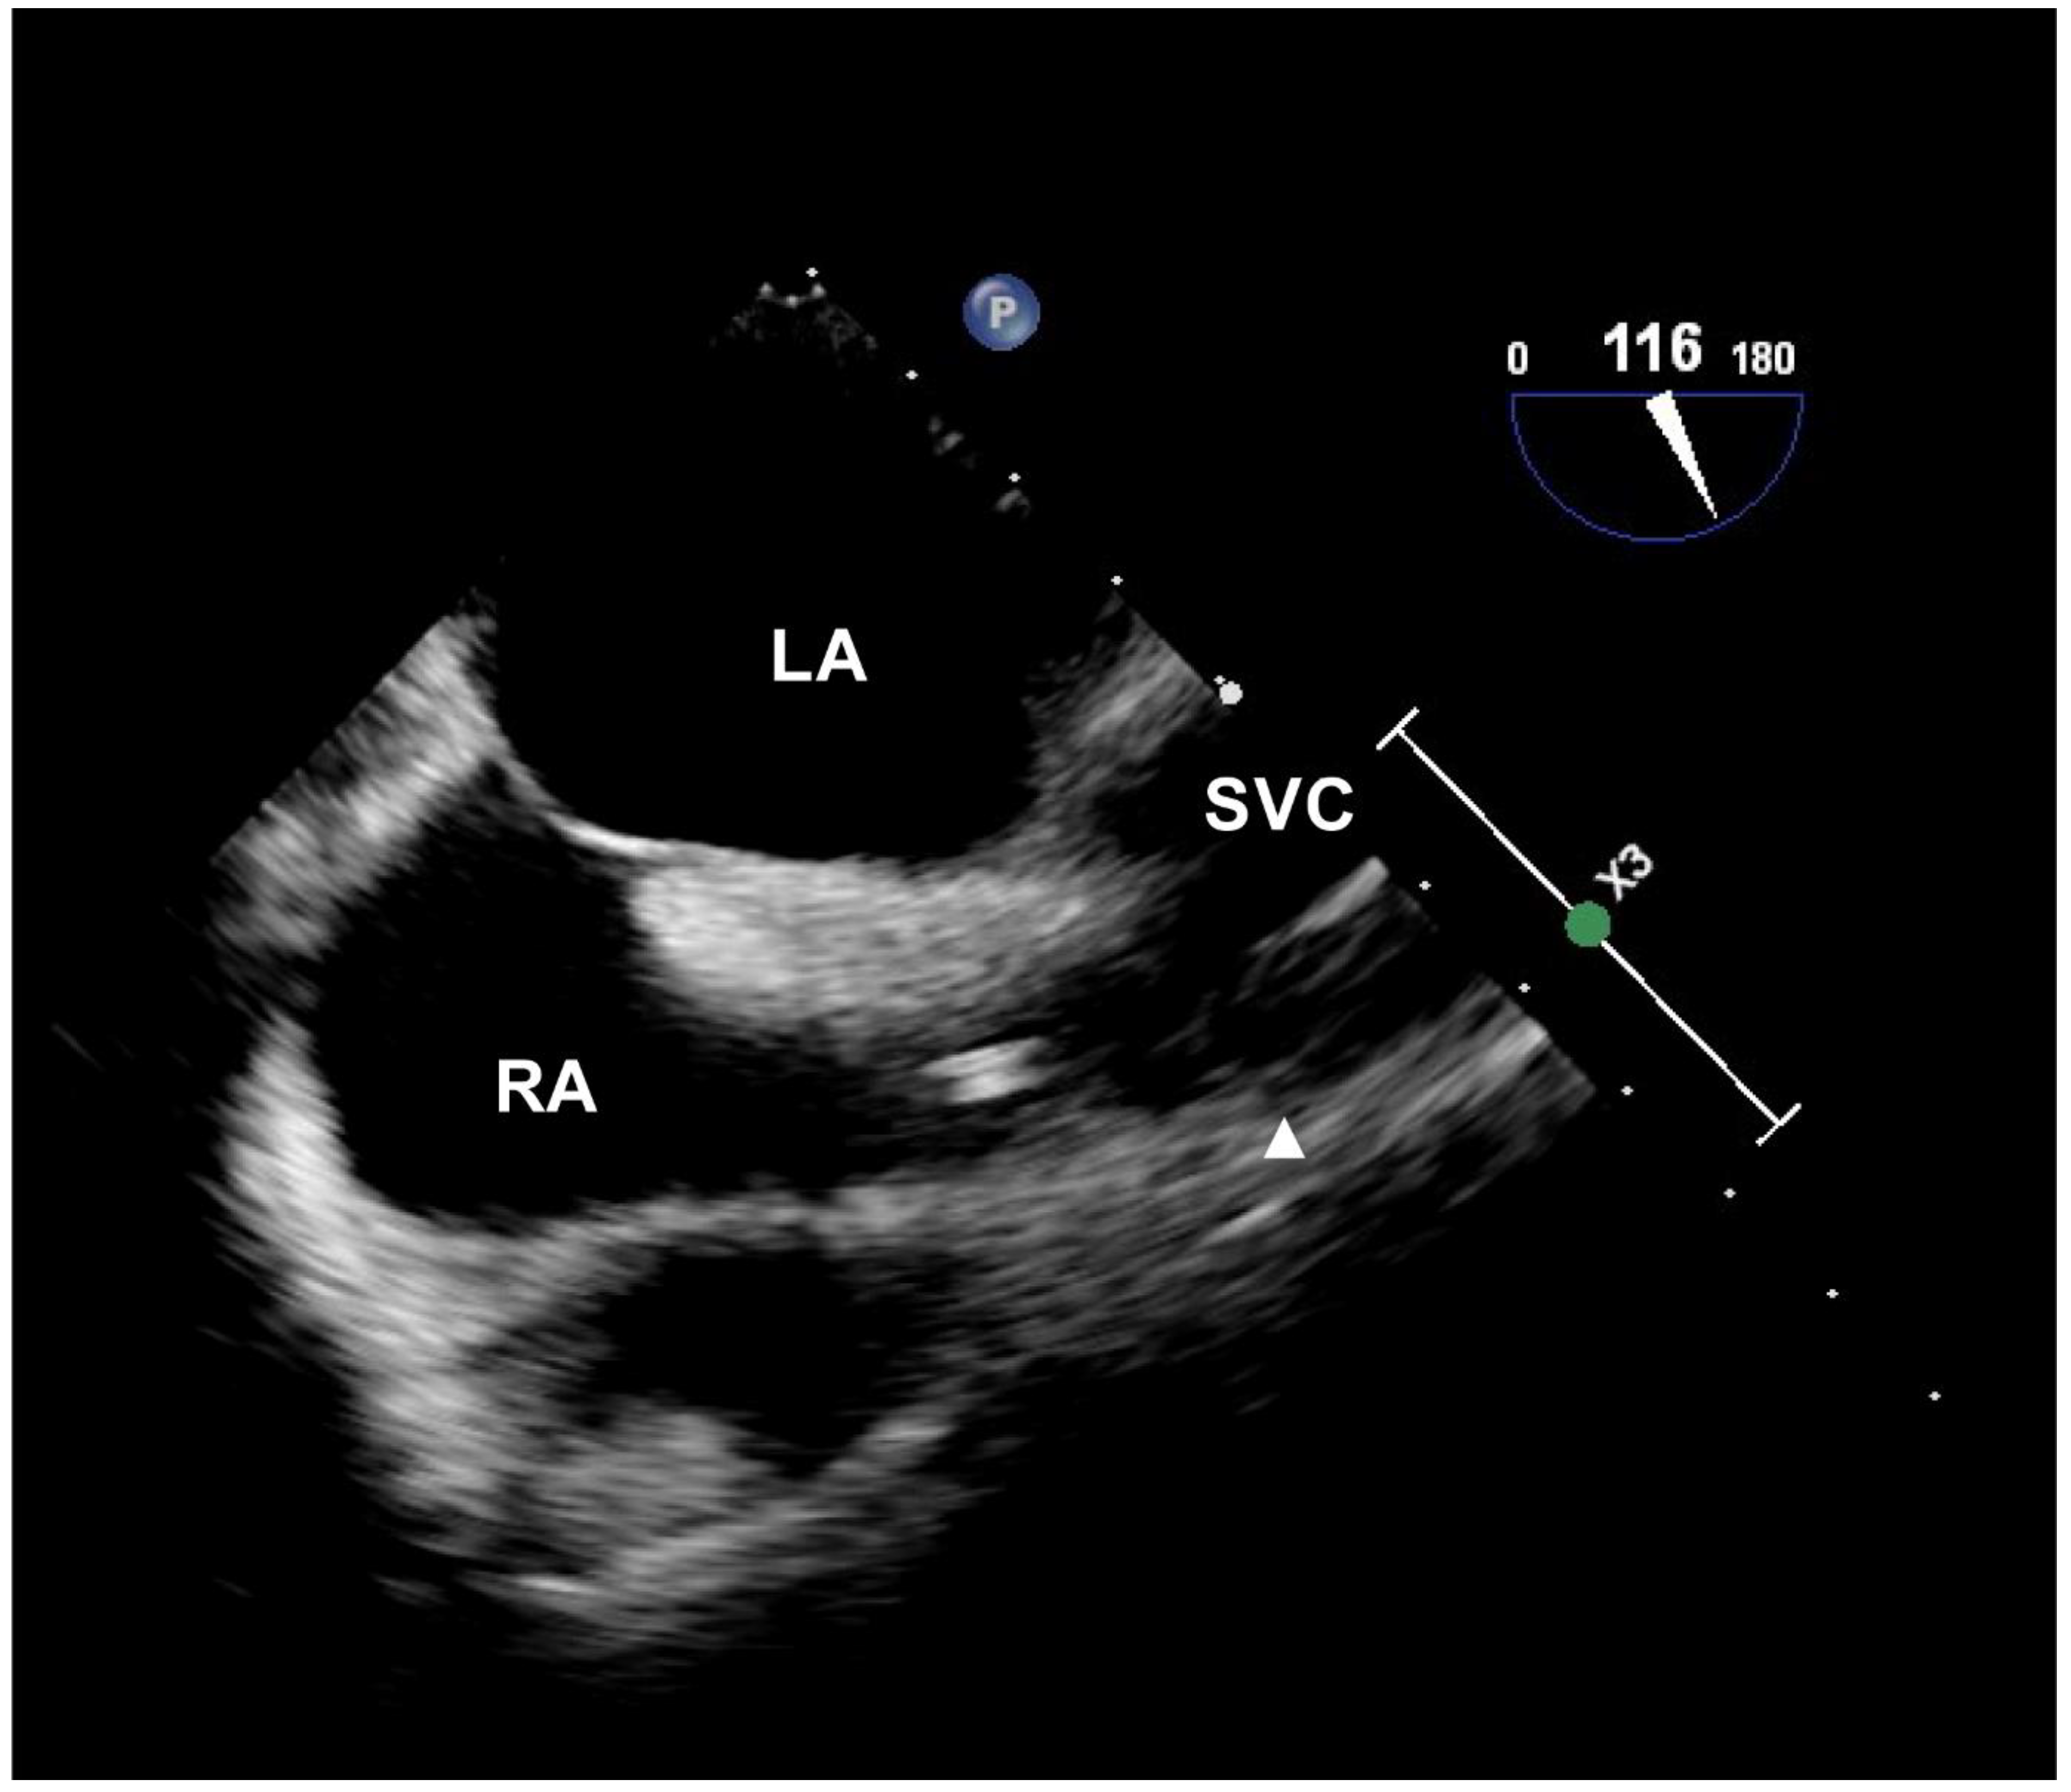

Following general anesthesia induction, an echocardiographic probe (X7-2t transesophageal transducer; Phillips, Andover, MA, USA) was inserted into the esophagus. During cannulation, the patient was maintained in the Trendelenburg position with arms abducted. After sterile preparation and draping, the puncture site in the infraclavicular area was pre-scanned using two-dimensional ultrasonography (Affiniti 70; Phillips, Andover, MA, USA) and a high-frequency linear transducer. After palpation of the sternal angle and identifying the right first intercostal space over the skin, the distance between the venous insertion point and the midpoint of the right first intercostal space just lateral to the sternal angle, and the distance between the first and third intercostal spaces just lateral to the sternum, were measured using a sterile graduated ruler. Central venous cannulation was performed by an ultrasound-guided in-plane approach in the longitudinal view. A 20 cm long, two-lumen catheter (Arrow G+ard Blue Central Venous Catheter; Arrow International Inc., Reading, PA, USA) was inserted using the Seldinger technique and secured at the determined depth according to the protocol for each group. On the bicaval view of echocardiography (Figure 2), accurate positioning of the catheter tip was assessed relative to the right atrial junction, which was assumed to be at the level of the upper border of the crista terminalis [13]. We also assessed the incidence of the angle of the tip > 40° in relation to the SVC, abutment of the tip with the SVC, and flow streams hitting the vascular wall using injections of agitated saline at the radiologically or topographically predetermined insertion depth.

Figure 2.

Echocardiographic image of catheter tip positioning. The catheter tip is identified as two parallel echogenic lines from the bicaval view. The solid triangle indicates the level of the upper border of the crista terminalis, defined as the echocardiographic junction of the SVC and the RA. Abbreviations: LA, left atrium; RA, right atrium; SVC, superior vena cava.